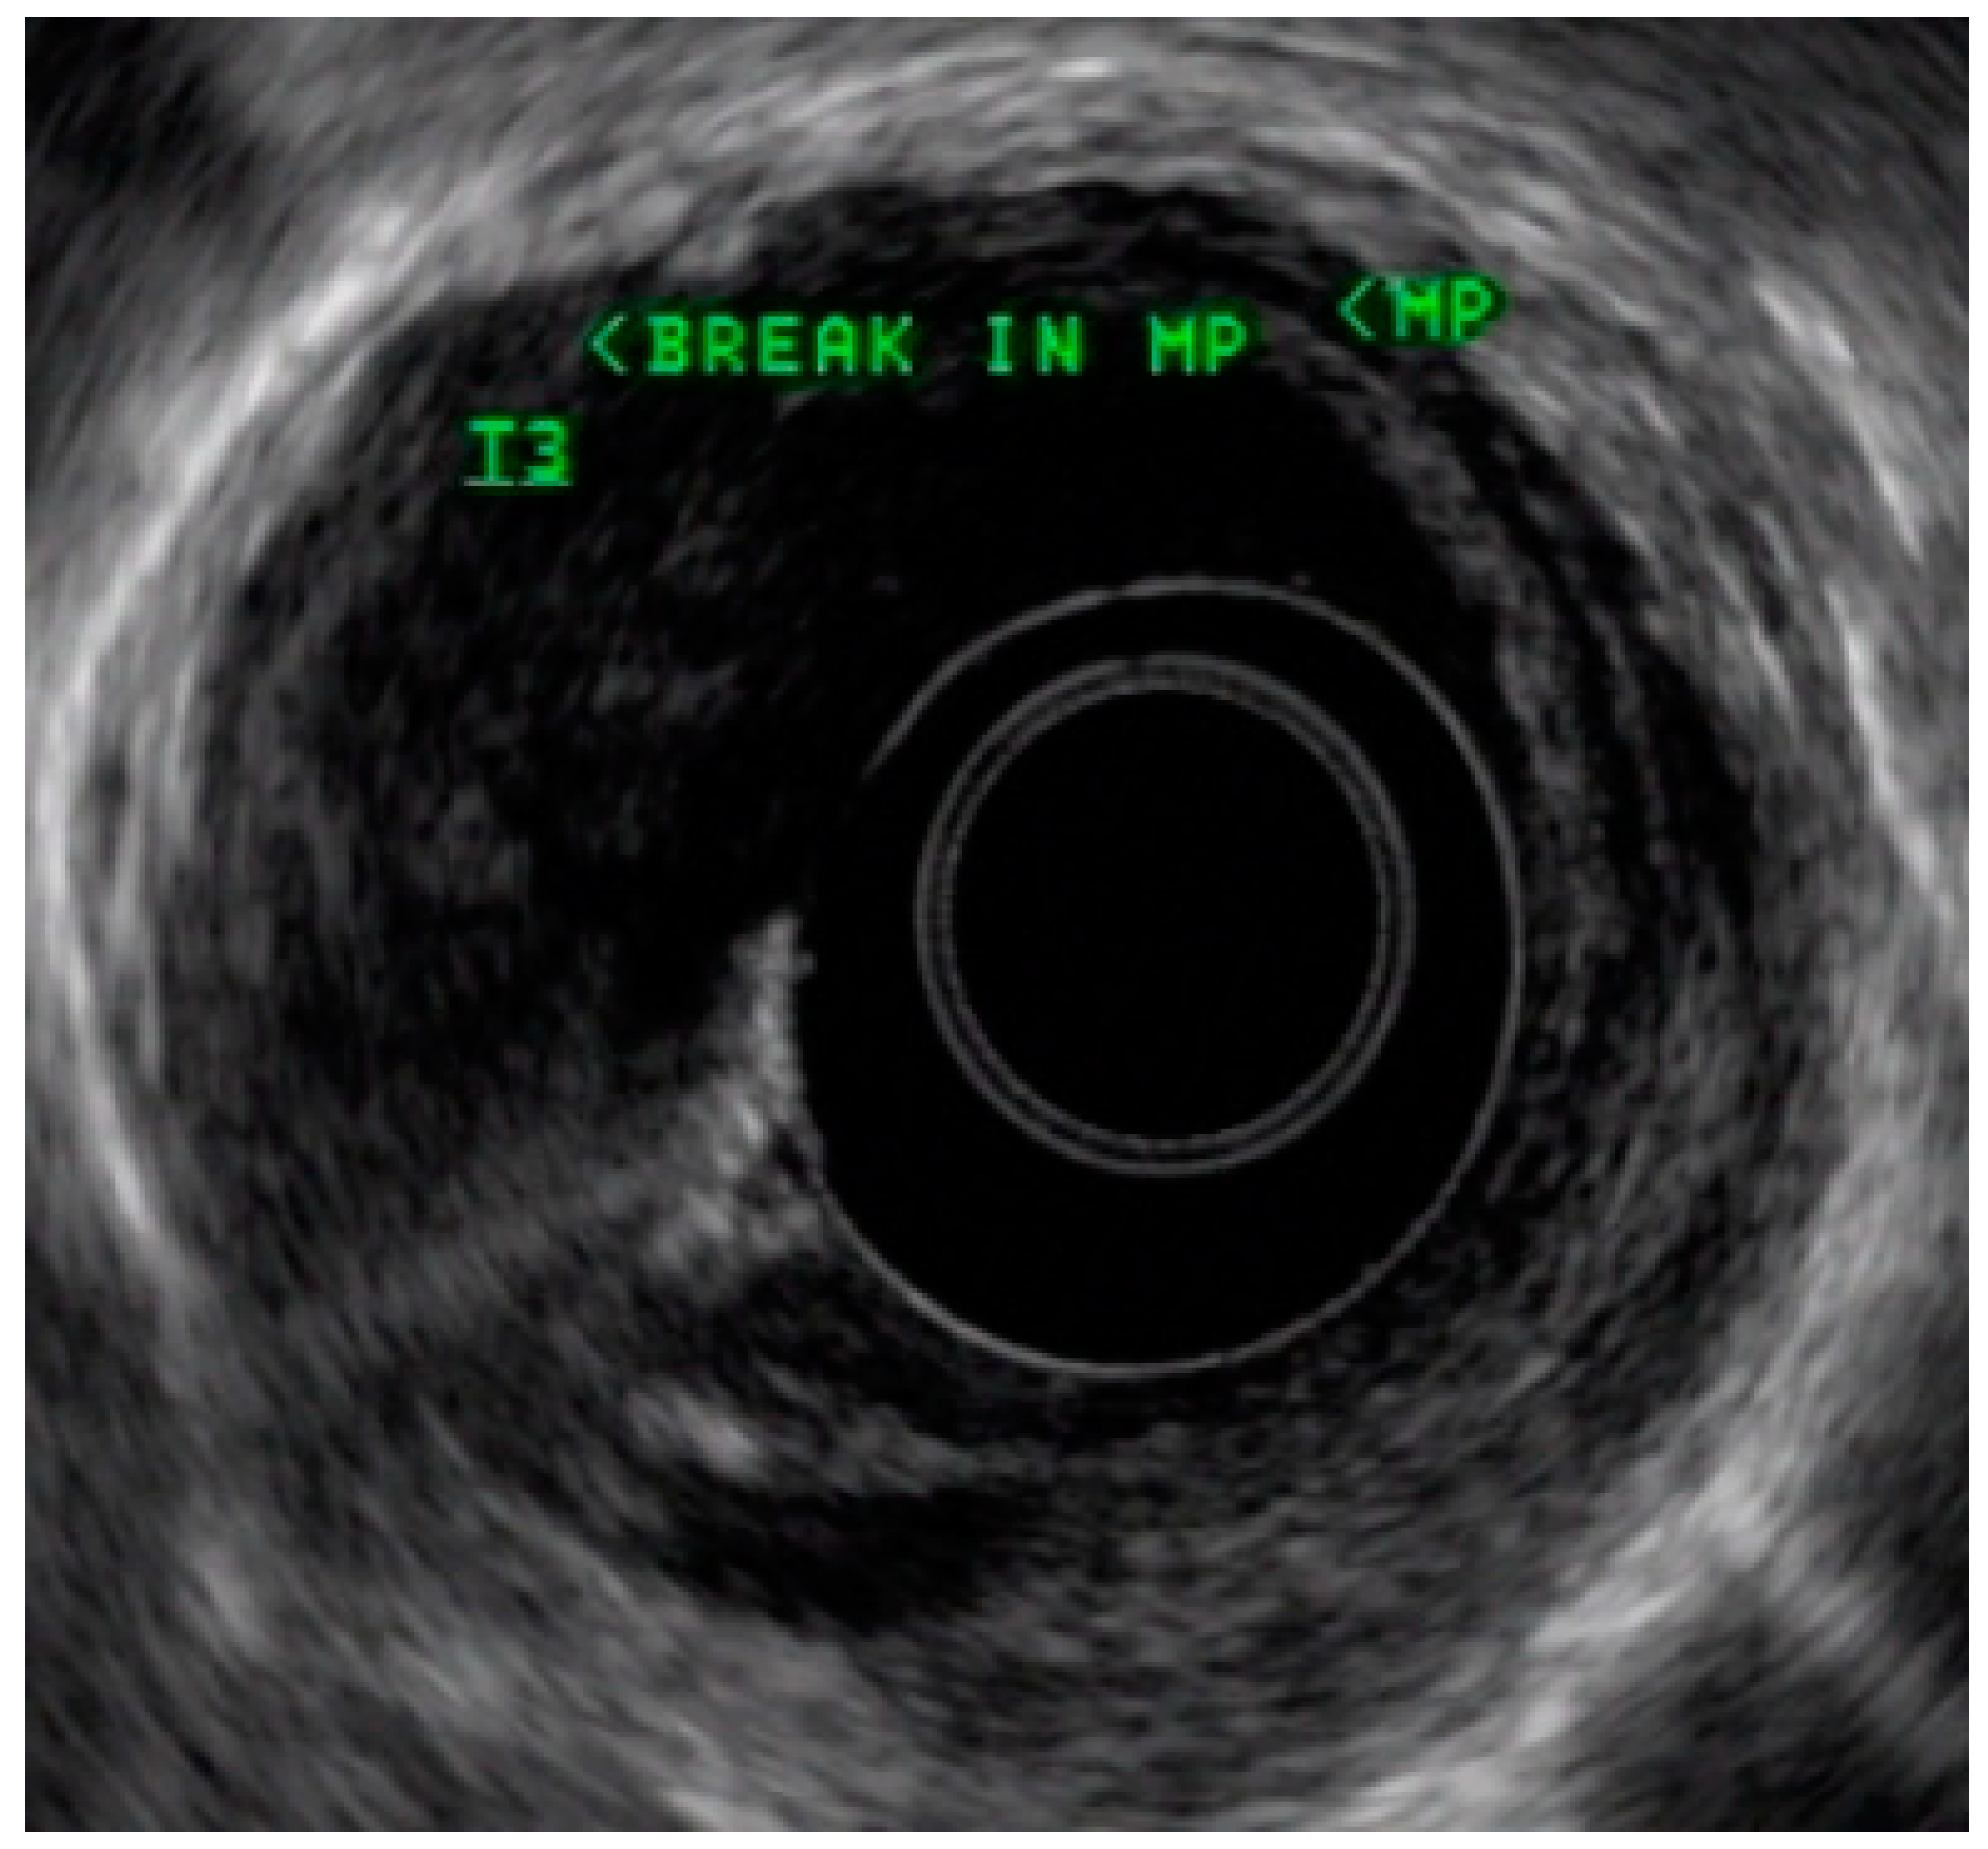

4.3. Endoscopic Ultrasound in Staging of Gastric Cancer

- Spolverato, G.; Ejaz, A.; Kim, Y.; Squires, M.H.; Poultsides, G.A.; Fields, R.C.; Schmidt, C.; Weber, S.M.; Votanopoulos, K.; Maithel, S.K.; et al. Use of Endoscopic Ultrasound in the Preoperative Staging of Gastric Cancer: A Multi-Institutional Study of the US Gastric Cancer Collaborative. J. Am. Coll. Surg. 2015, 220, 48–56. [Google Scholar] [CrossRef] [PubMed]

- Mocellin, S.; Pasquali, S. Diagnostic accuracy of endoscopic ultrasonography (EUS) for the preoperative locoregional staging of primary gastric cancer. Cochrane Database Syst. Rev. 2015, 2015, CD009944. [Google Scholar] [CrossRef]

- Redondo-Cerezo, E.; Martínez-Cara, J.G.; Jiménez-Rosales, R.; Valverde-López, F.; Caballero-Mateos, A.; Jérvez-Puente, P.; Ariza-Fernández, J.L.; Úbeda-Muñoz, M.; López-De-Hierro, M.; De Teresa, J. Endoscopic ultrasound in gastric cancer staging before and after neoadjuvant chemotherapy. A comparison with PET-CT in a clinical series. United Eur. Gastroenterol. J. 2017, 5, 641–647. [Google Scholar] [CrossRef]